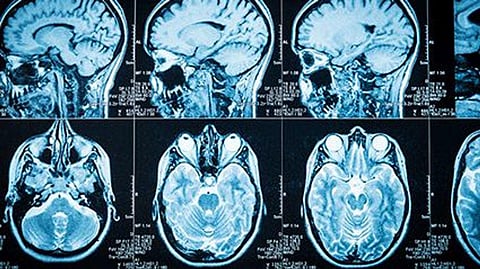

Brain scans from the 60 concussion patients were compared to those taken from 60 people with no history of concussions or post-traumatic headache.

The scans showed that, compared to folks who'd never been concussed, those with a history of concussion had higher levels of iron in various brain areas. Iron levels seemed to mount as time after the concussion went on.